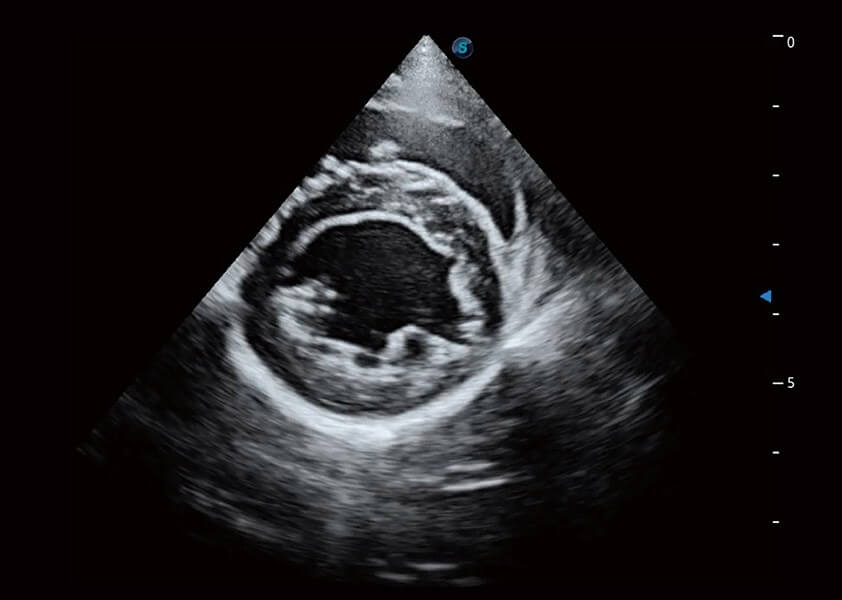

(犬)四腔心血流

(犬)乳头肌短轴

(猫)二尖瓣M型